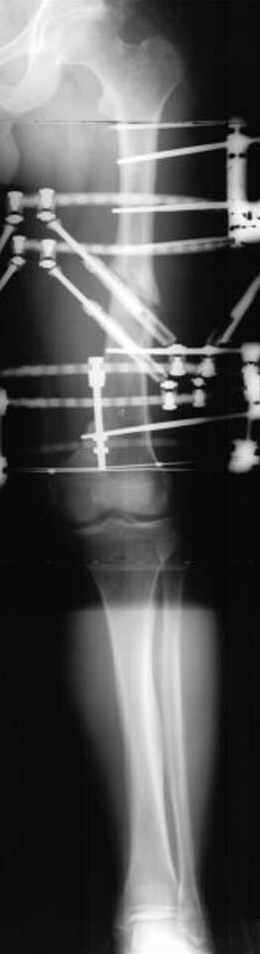

Отправитель: Djoldas Kuldjanov 23 Ноябрь 2004, 18:21

пластическая модель; и коррекция бедра аппаратом Илизарова.

Узкий к-м канал - тонкий гвоздь- усталостный перелом дистальных винтов - развитие нестабильности и как ее результат остеолиз вокруг гвоздя - деформация анатомической оси бедра. Похоже, что я понял почему аппарат, а не новый гвоздь:-)